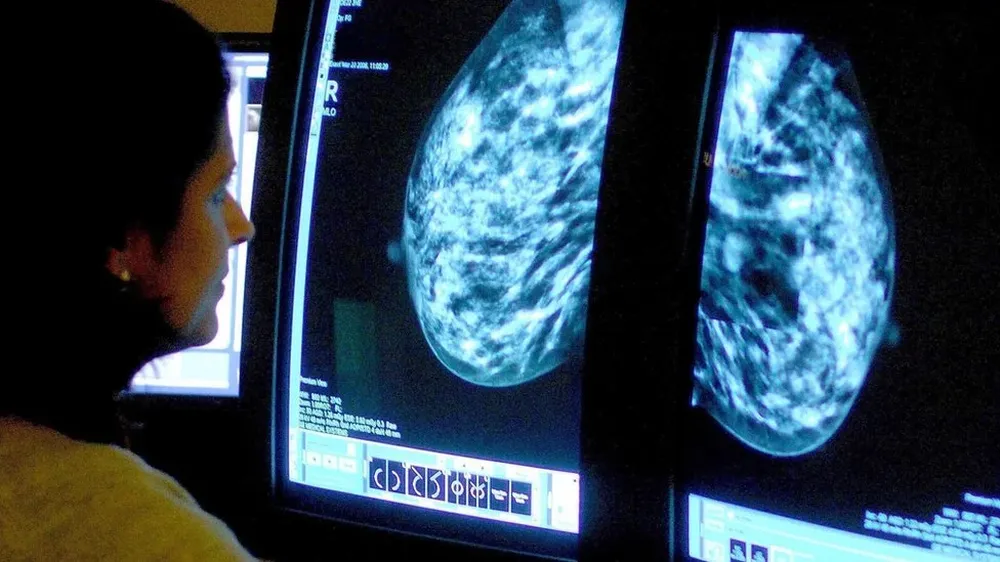

Los especialistas destacaron que la IA ya se ha incorporado en el ámbito médico en la región, apoyando la reducción de las listas de espera, facilitando el acceso a tratamientos y diagnósticos y contribuyendo al análisis de imágenes en la detección del cáncer de mama. Específicamente en países como Colombia, Argentina y Brasil ya se están utilizando diferentes algoritmos en estudios de imagen, una tecnología que permite ayudar a los médicos a identificar patrones histológicos en las biopsias.

De acuerdo con las cifras del Global Cancer Observatory, base estadística de cáncer de la Organización Mundial de la Salud (OMS), el cáncer de mama es la segunda causa de muerte por tumores malignos en mujeres latinoamericanas.